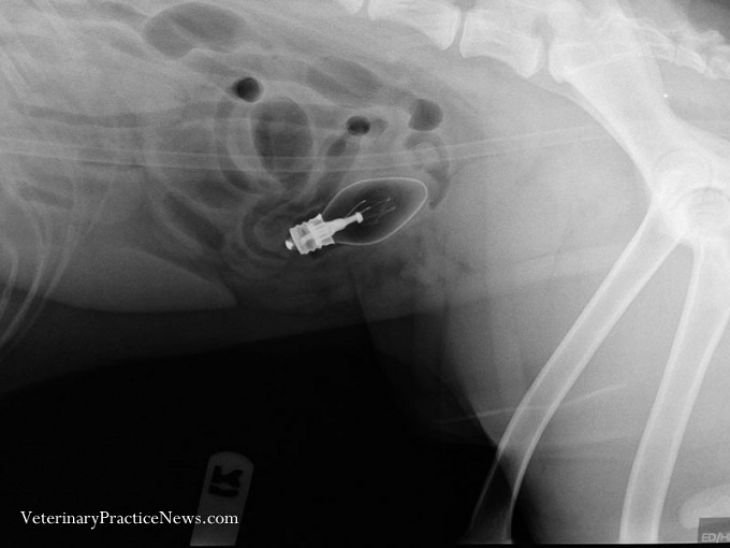

Žiarovka

Zlatý retriever vracal dva dni pred tým, ako röntgen dokázal, že prehltol žiarovku. Žiarovku sa podarilo neporušenú vybrať z jeho tela von.

(Zdroj: Golf Rose Animal Hospital via Veterinary Practice News)